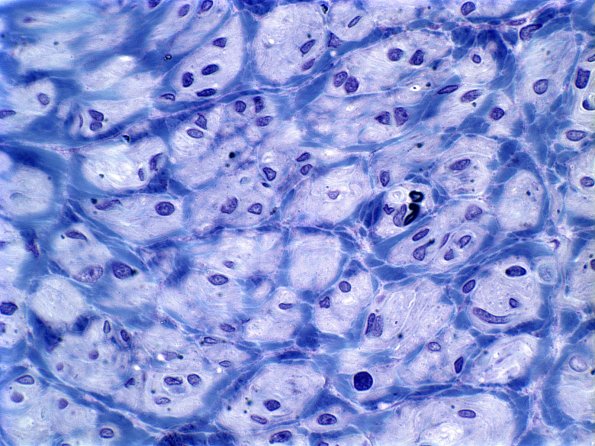

Washington University Experience | PERIPHERAL NEUROPATHY | 20 PSEUDO-ONION BULBS | 2E3B (Case 2) Plastic 3

2E3B (Case 2) Plastic 3

In these areas the nodular collections of Schwann cells do not contain individual myelinated axons. (Plastic section),